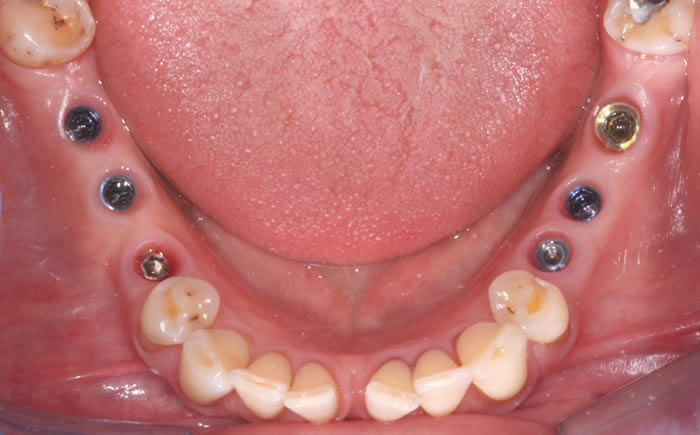

Full arches of teeth replaced by dental implants

Case Two (8 images)

Full set of lower teeth fixed onto five dental implants.